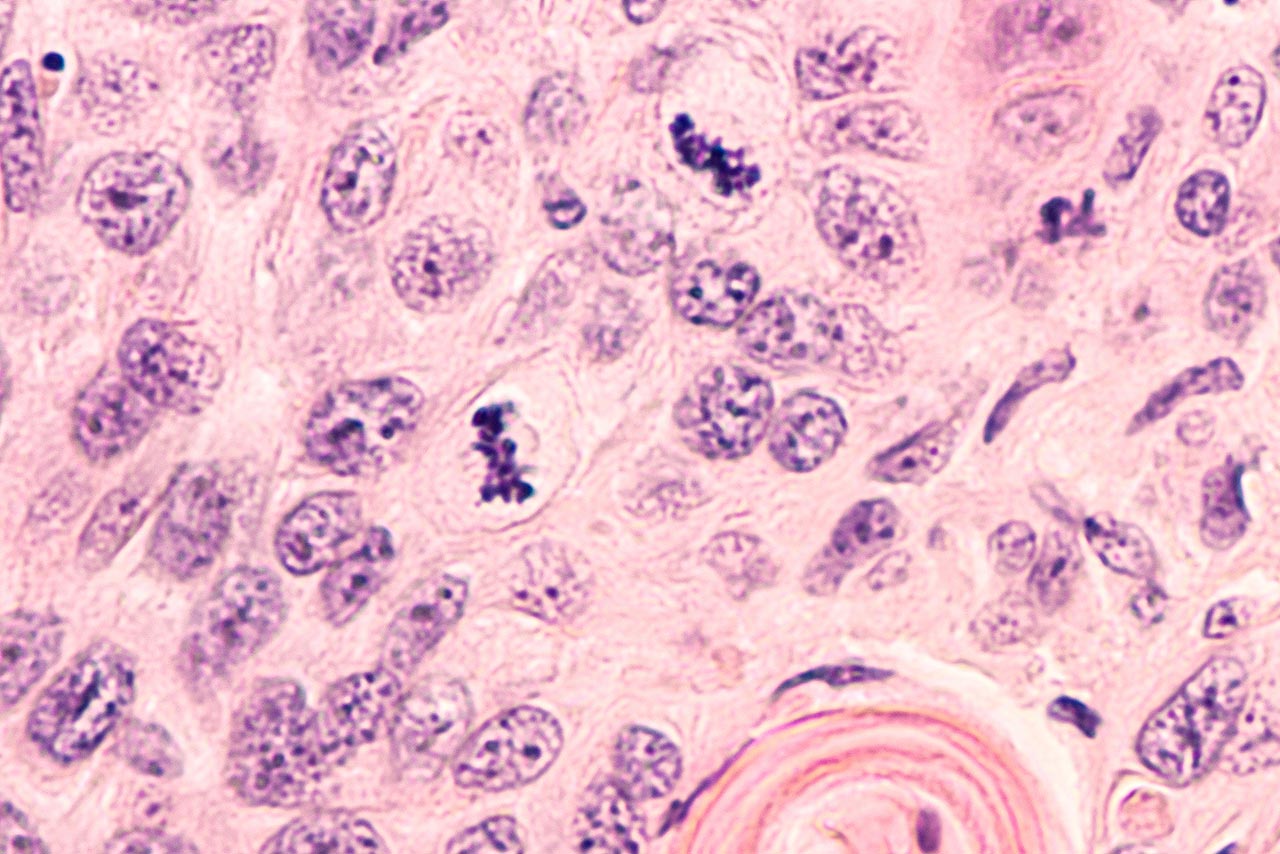

The ionizing radiation passing through a living cell may damage or even kill it. The damage may be direct (radiation affects the DNA) or indirect (radiation produces free radicals that will subsequently damage the DNA). A cell may repair minor defects, such as damage to one-half of a DNA chain. If the damage cannot be repaired, the cell dies. A single dead cell does not pose any threat to the organism. Damaged DNA that does not lead to cell death may result in mutation and altered behavior of the cell, including all its descendants, and can possibly trigger cancer.